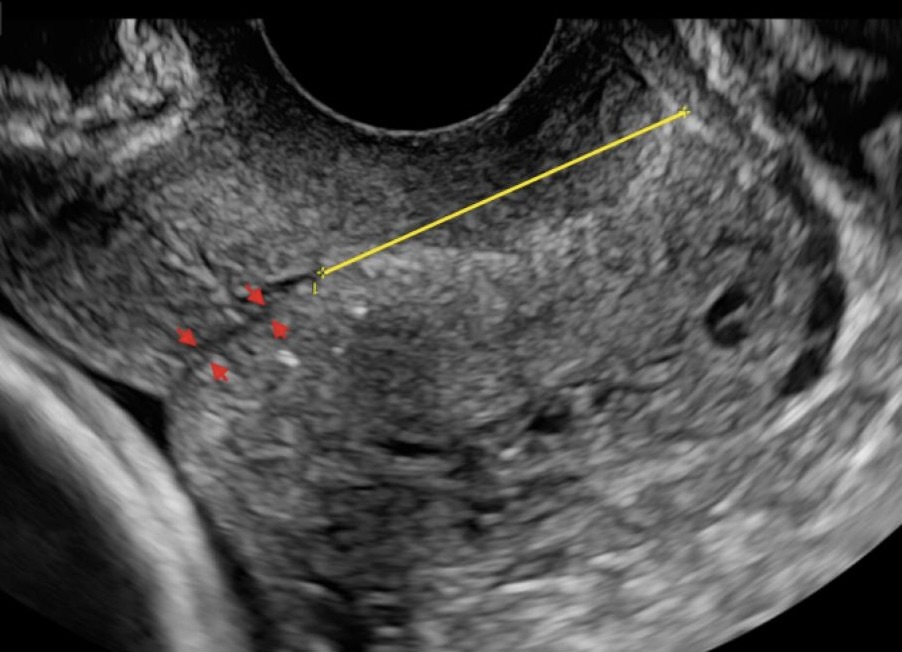

5. Previous full dilatation caesarean section

With more than 50% of babies in the UK now born by caesarean section, referrals to preterm clinics following full dilatation caesarean section are increasing. The challenge with imaging the cervix in this scenario is that the caesarean section incision can be confused with the internal os.  It is therefore important to identify the incision and consider whether the cervix extends beyond it as in figure 3.

Figure 3. Example of caesarean incision in a long cervix

6. Uterine didelphis

Congenital uterine anomalies are a risk factor for preterm birth; however women are not always aware of their specific uterine anomaly. It is therefore always good practice to consider a uterine anomaly, such as uterine didelphis, when the cervix has an unusual appearance. If you suspect two cervical canals on longitudinal section, turn into transverse section to confirm the presence of two cervical canals (Fig 4).

Figure 4a. Longitudinal section showing two cervical canals

Figure 4b.  Transverse section showing to two cervical canals in cross section.